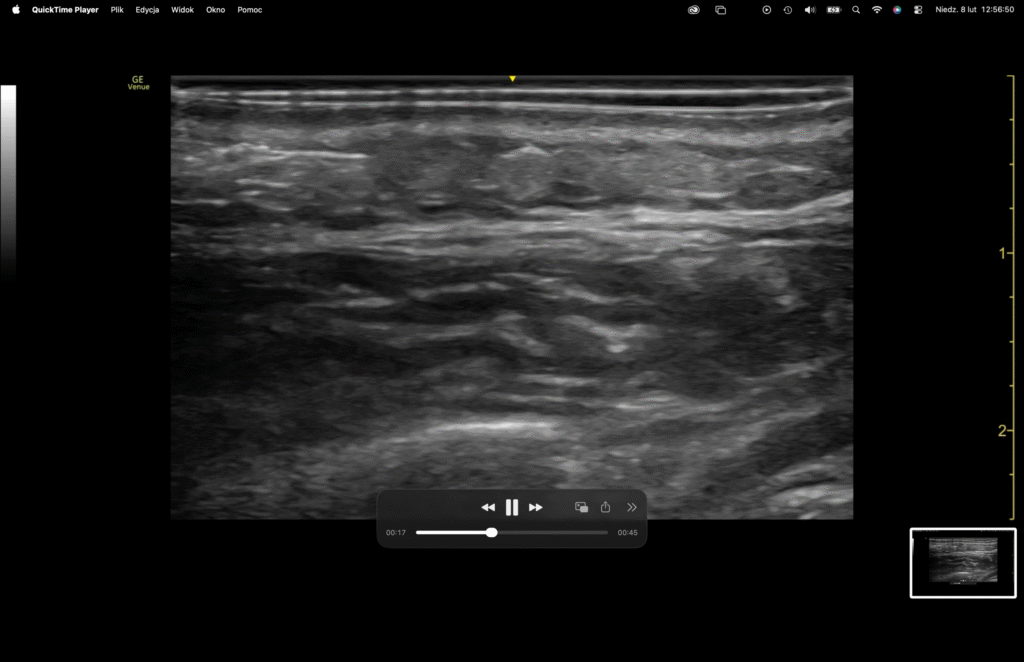

W badaniu ultrasonograficznym (ryc. 3) w warstwie subcutis, obserwujemy podłużną, jednorodną, mass-like strukturę o charakterze hipoechogenicznym, wyraźnie jednak odgraniczoną od otaczającej tkanki podskórnej. MEC Regenerate®, zdeponowany w tkance podskórnej, powyżej powięzi przyuszniczo-żwaczowej, inaczej SMAS, harmonijnie układa się pomiędzy delikatnymi strukturami retinacula cutis.